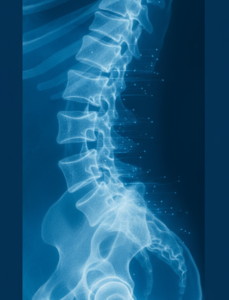

The spine is formed by a bony, weight-bearing column of vertebrae. When young and healthy, these bones can withstand significant amounts of pressure, but with aging bones lose density, gradually becoming more brittle and susceptible to fracture.

Spinal compression fractures occur when the bone structure becomes so weak and the vertebra virtually collapses on itself, creating a wedge-like shape. This can cause a significant amount of pain and structurally can cause your posture to stoop forward (kyphosis) and chronically can give you the appearance of a hunchback. Both these factors can leave you bedridden and make it difficult for you to take a deep breath making you more susceptible to infections such as pneumonia.

Over time, you can become shorter with more limited motion of your spine with the development of a dowager’s hump (hunchback) and a stomach that protrudes (i.e. sticks out) which can decrease your appetite.